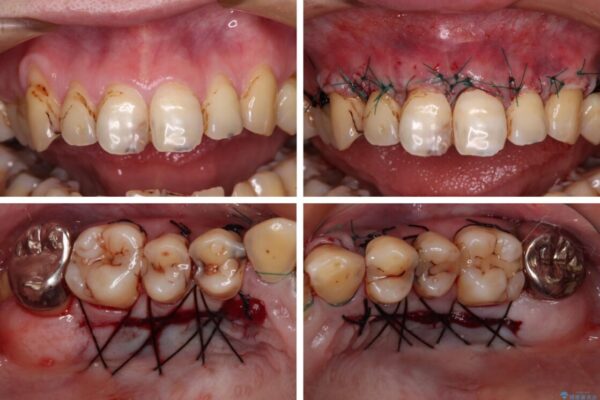

上下前歯や奥歯の虫歯治療を希望して来院された患者様です。

全顎的にむし歯が多く、根管治療の必要な奥歯や、審美的に気になっている前歯を中心にオールセラミッククラウンにて補綴治療を行うこととしました。

上顎前歯は歯肉退縮により歯根が露出していたため、事前に歯肉移植術により根面被覆を行い、その後にオールセラミッククラウンを装着することとしました。

治療途中

• むし歯だらけの前歯をオールセラミッククラウンできれいに 治療途中画像